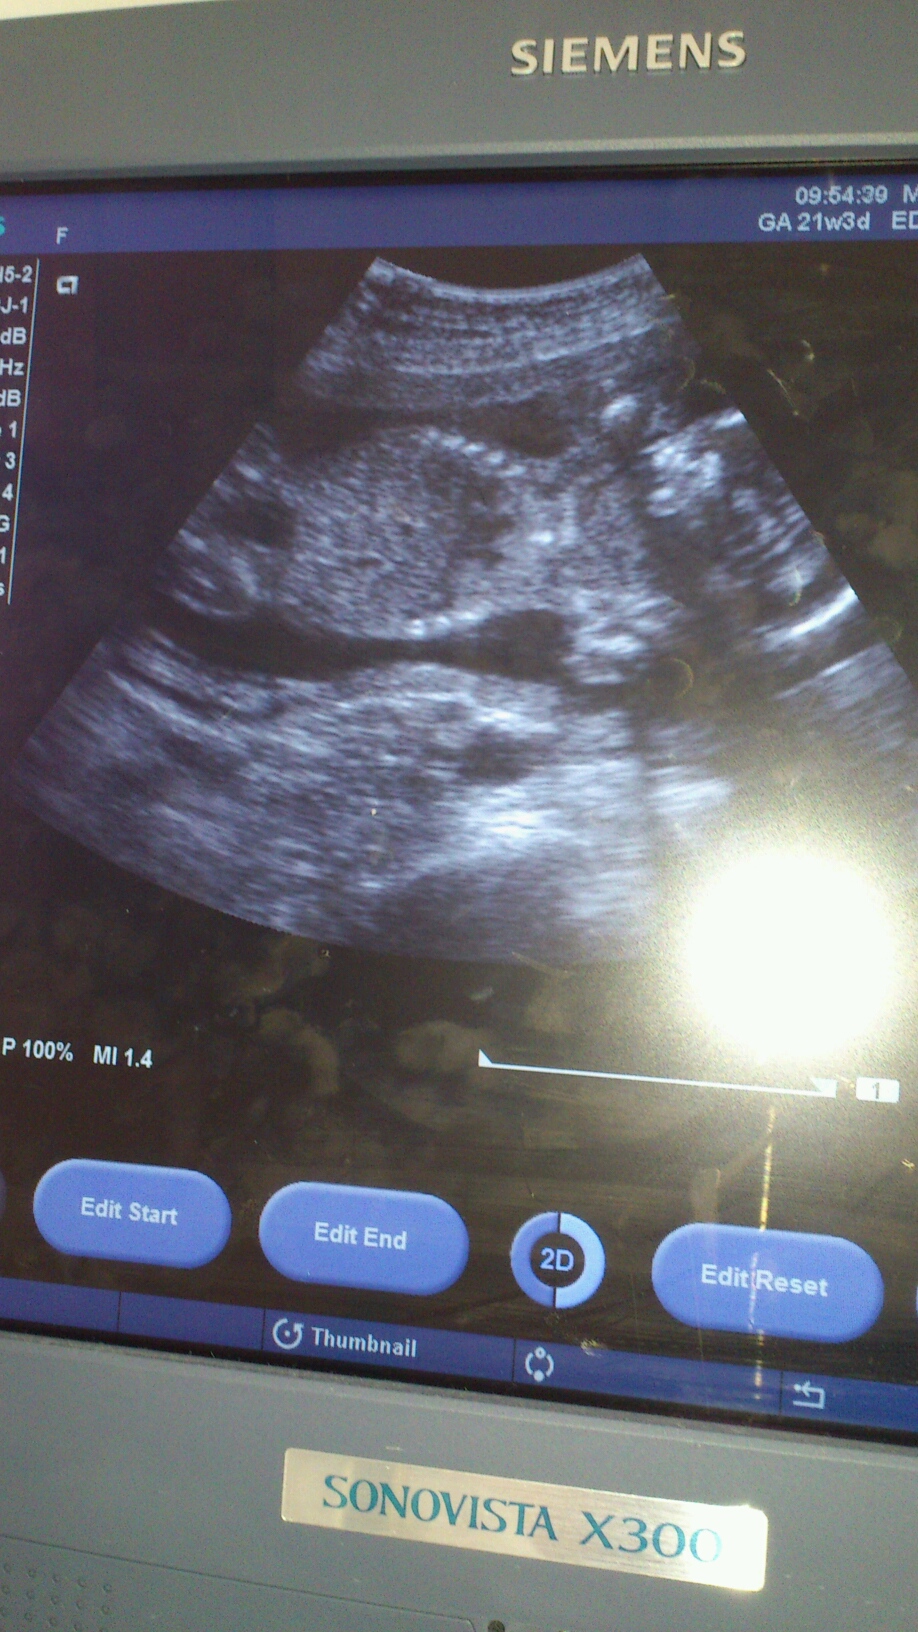

妊婦ちゃん 6ヶ月

こないだで 6ヶ月に 入りました。

頭周囲から 計算して

順調な 成長みたいです!

来月から ベビーの体重も解るみたい

性別を 聞き忘れ(--;)

あと 1ヶ月 気になるわ♪

まあ 元気に 産まれてきてくれたら

どちらでも いいかな